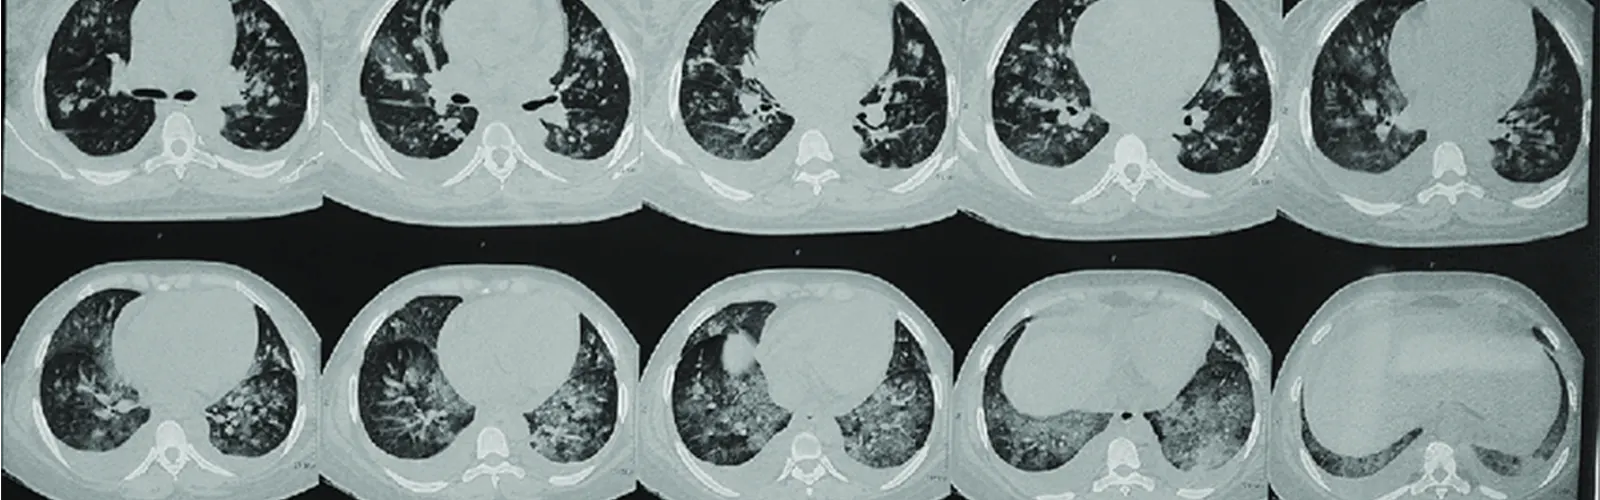

Non-contrast computed tomography (NCCT) of the chest is a type of medical imaging procedure that uses X-rays and computer technology to create detailed images of the chest without the use of a contrast agent. Here are some ways NCCT chest can be helpful in the follow-up of patients:

Monitoring the progression of lung diseases: NCCT chest can be used to monitor the progression of lung diseases such as chronic obstructive pulmonary disease (COPD), bronchiectasis, and interstitial lung diseases. By comparing the NCCT chest scans over time, doctors can identify changes in the size, shape, and density of the lungs that may indicate disease progression.

Detecting the recurrence of lung cancer: NCCT chest can be used to detect the recurrence of lung cancer after treatment, such as surgery or radiation therapy. By monitoring the chest with regular NCCT scans, doctors can identify any new or growing tumors that may require additional treatment.

Evaluating the response to treatment: NCCT chest can be used to evaluate the response of lung diseases to treatment, such as chemotherapy or immunotherapy. By comparing the NCCT scans before and after treatment, doctors can assess the effectiveness of the treatment and make adjustments as needed.